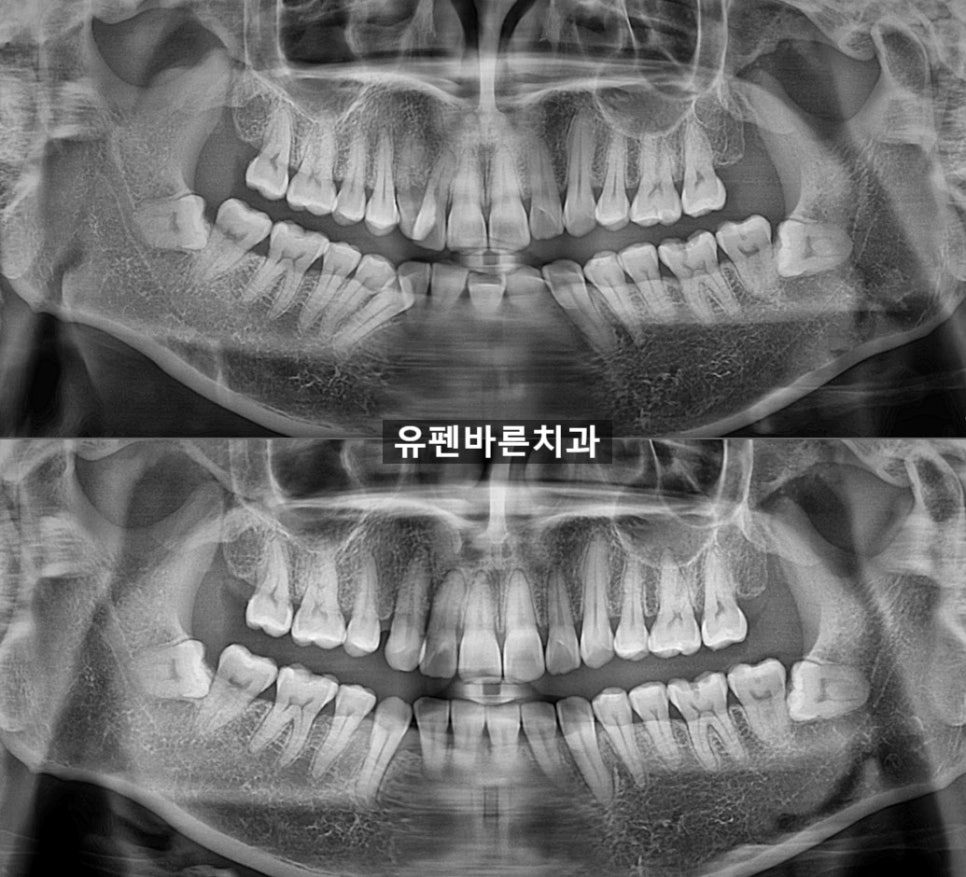

그렇다면

위 아래

사진도 같이 보실게요

9개월 전에 비해

확연히 가지런해진

모습을

확인해보실수 있습니다 :)

엑스레이

전, 후 사진을 보니

치아 뿌리 상태와

잇몸 상태는

여전히 좋습니다!!